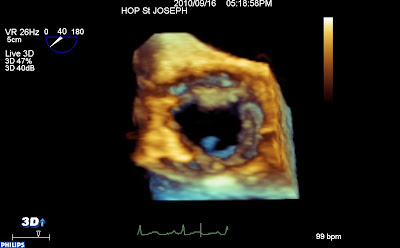

En ETO 3d, versant aortique, les dégâts valvulaires sont au premier plan, et en arrière plan, la masse mobile qui vient dire bonjour…

vue aortique 3d from fish Nip echocardiographie on Vimeo.